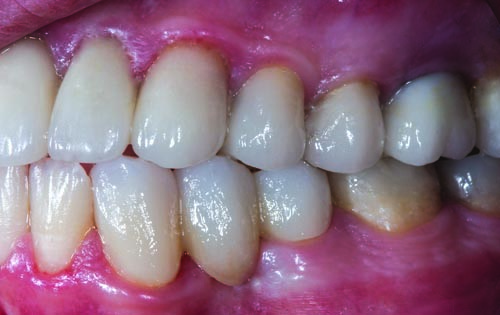

Fig. 3: The preoperative right lateral view shows evidence of the failing mesial/occlusal/distal (MOD) amalgam restorations in teeth #2, #4, #5, #29, #30, #31 and #32, as well as the need to replace missing tooth #3.

Figs. 34–36. The three subsequent and final appointments were scheduled two weeks apart to focus exclusively on completing the restoration of the mandibular arch. In particular, the sixth appointment was dedicated to final preparations and impression taking on teeth #18 through #31. Two weeks later, the definitive IPS E.max crowns for teeth #18, #19, #30 and #31 and the full Katana zirconia bridges for teeth #20 through #22 and teeth #27 through #29 were inserted during the seventh appointment. Any adjustments required were performed two weeks later during the eighth scheduled appointment.